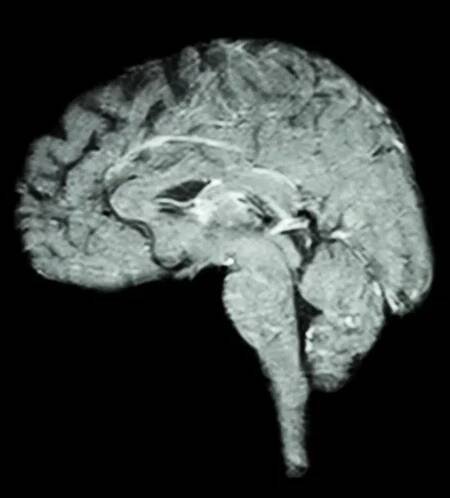

Magnetická rezonance (též MR, MRI, z anglického „magnetic resonance imaging“) je zobrazovací technika používaná především ve zdravotnictví k zobrazení vnitřních orgánů lidského těla.

Magnetické rezonanční zobrazování (také označovaná jako MRI - zkratka z Magnetic Resonance Imaging) je test, který využívá silné magnety, rádiové vlny a počítač pro vytváření detailních snímků uvnitř těla.

MR (MRI - magnetic resonance imaging) je vyšetřovací metoda, využívající k zobrazení jednotlivých tkání měření změn magnetických momentů atomových jader.